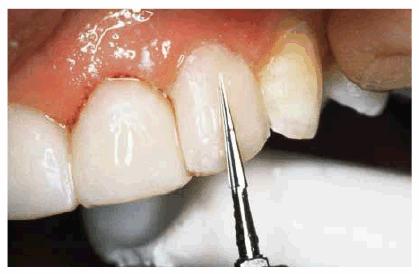

The Protruding Tooth

In restoring a crowded labially positioned incisor, careful preparation can

make the protruding tooth appear to be in a more lingual position. Care must be

taken to avoid a short preparation. The labial surface is reduced as far as

possible without damaging the pulp; very little tooth structure is removed from

the linguoincisal surface (Figures 24-8A, and 24-8B). It is extremely important not to reduce the

incisogingival height until the preparation is essentially complete. This will

help avoid a short preparation. If the labial protrusion is so extreme that the

pulp may become involved, the dentist may perform vital pulp extirpation.2

Such radical procedures should be undertaken only when appearance is extremely

important and the patient is completely aware of the possible consequences and

has signed an informed consent for treatment.

Figure 24-8A: The labial surface is reduced as far as possible without damaging the pulp. It is extremely important not to reduce the incisogingival height until the preparation is essentially complete.

Figure 24-8B: The crowded labially positioned incisor requires a careful preparation to make it appear to be in a more lingual position.